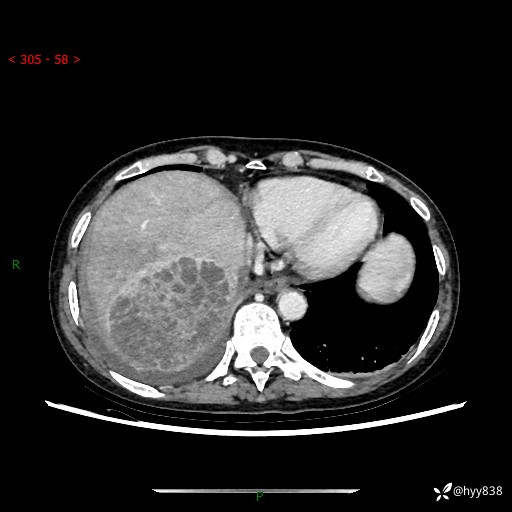

病例老年女性,发热来诊。如此“蜂窝煤”,治疗很棘手---结果公布~

性别:女

年龄:53岁

简要病史:发热(门诊急诊患者)

上腹部CT平扫